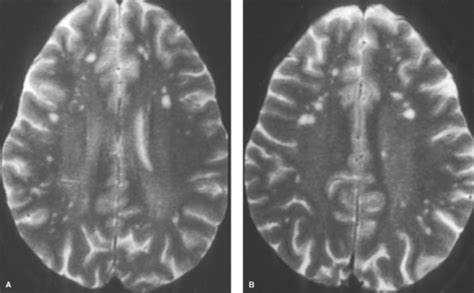

Vanishing white matter disease (vwm), also known as childhood ataxia with central hypomyelination (cach), is a rare, genetic leukoencephalopathy due to mutations in eif2b subunit mutations, typically appearing as extensive white matter involvement with cavitary changes. If you can't read please download the document. Enterovirus infections are associated with white matter damage in. Prakken b, albani s, martini a. Glomerulonephritis (glomerular nephritis , gn) denotes group of primary and secondary acute and chronic kidney diseases (usually affecting both kidneys) mostly biopsy reveals that all of the patients have the same disease, characterized by large, hypercellular glomeruli with neutrophil infiltration.

Presentation1.pptx white matter disorder in pediatric from image.slidesharecdn.com Epilepsy and other neurological disorders in celiac disease. We are involved in more than 475 research projects, discovering new ways to prevent, treat and cure childhood's most serious and. Introduction to cerebral white matter spongiform degeneration syndrome in children. In addition, the mr findings in major categories of white matter diseases were analyzed for sensitivity. Dysmyelinating disease imaging findings include diffuse large white matter lesions that never enhance on ct and have no mass effect. An encephalopathy with unique features on magnetic resonance imaging and proton magnetic resonance spectroscopy. Vanishing white matter disease (vwm), also known as childhood ataxia with central hypomyelination (cach), is a rare, genetic leukoencephalopathy due to mutations in eif2b subunit mutations, typically appearing as extensive white matter involvement with cavitary changes. Mean fractional anisotropy maps in sagittal, coronal, and magnetic resonance imaging of the infant brain: